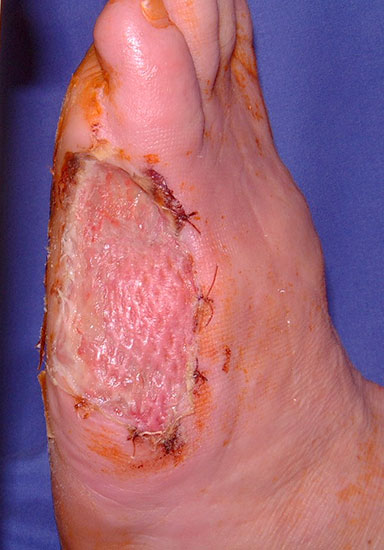

Die Knochenenden müssen so gestaltet werden, dass sie keinen Druck auf die Haut aus­üben können. Wenn sich die Wundränder nicht durch Nähte verschließen lassen (z.B. nach Infektion), wird in den nicht belasteten Regionen eine Spalthautdeckung vorgenommen (Abb. 28, 29), wenn eine infektfreie Granulation vorliegt.